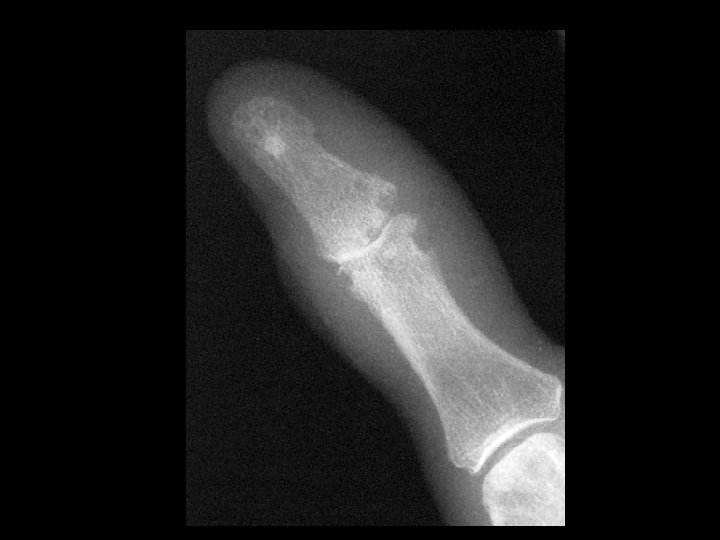

Hyperparathyroidism & Acro-osteolysis • Findings: – Erosion and resorption of digital tufts – Osteopenia with coarse trabecula – Subperiosteal bone resorption along the radial side • ddx: (acro-osteolysis) – Frostbite / Electrical burn – Polyviny chloride exposure – Pyknodysostosis – Neuropathy – Psoriatic arthritis – Hajdu-Cheney syndrome